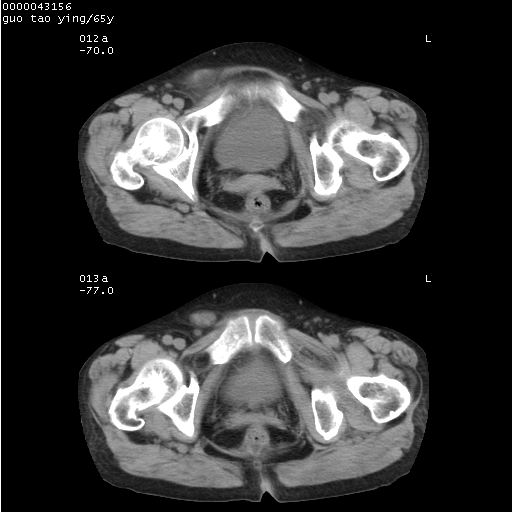

以下是引用黑白光影在2008-1-30 13:22:00的发言:[br]支持左耻骨骨折。[br]未见骶骨骨质明确破坏改变。[br]经楼主提示(勿局限于外伤)。考虑为右侧腹股沟直疝。[br][br][br][br]